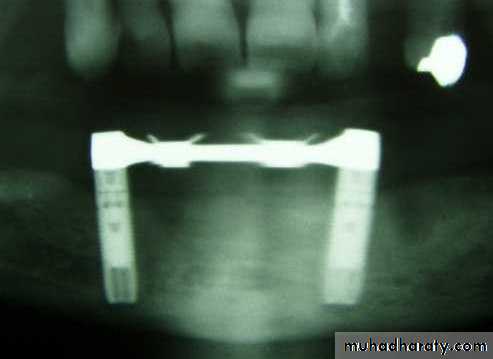

Transosteal / Transosseous Implant

Also called as Staple Bone Implant, Transmandibular ImplantPenetrates both cortical plate and passes through the entire thickness of the alveolar bone

Use restricted to anterior area of mandible

It is not used much any more because they necessitate an extraoral surgical approach.